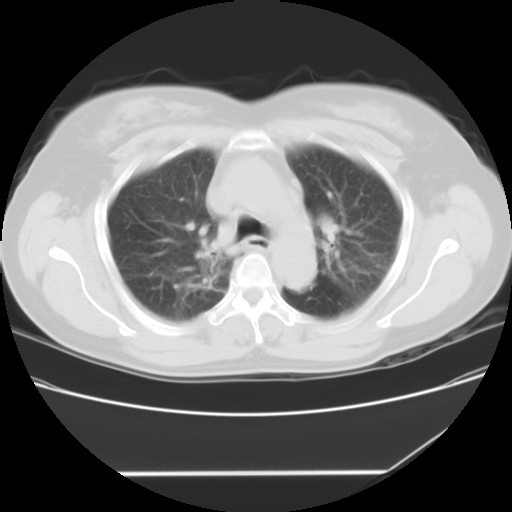

标题: CT24018:女性,62岁,咳嗽4年,无热,胸部CT扫 [打印本页]

女性,62岁,长期咳嗽,既往从事工作有粉尘接触,有高血压病史,110/150mmhg,近日咳嗽加重,脸面浮肿,请大家帮看下,

1、尘肺;2、慢性支气管炎合并肺部感染;3、心影增大(左房、左室大),考虑高血压性心脏病。

慢支并肺部炎症;右肺结核球?主肺动脉、右肺动脉影不宽,右心室不大,不支持肺心病;无心包积液。

间质性肺炎,有纤维化趋势。

1)慢性支气管炎并肺部感染、肺气肿。2)肺间质纤维化。